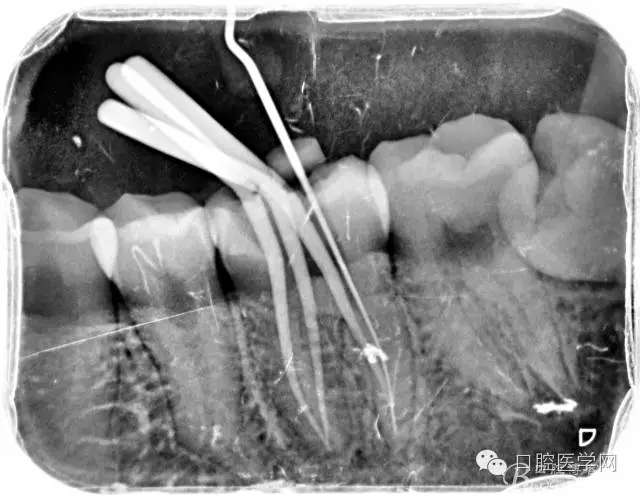

根管的解剖界限是从髓室根管入口到根尖部牙本质- 牙骨质交界处(生理性根尖孔) 。理想的根管充填应该是对生理性根尖孔冠方以上进行严密的三维封闭。临床上根据X线牙片判断根管充填的质量。牙片上充填材料与根管壁紧密接触一般被认为充填严密。关于充填止点,由于牙本质- 牙骨质界离根尖孔外表面平均距离为0. 5~0. 7 mm,同时相当多的根尖开口并不位于X线片的根尖处。因此临床上认为材料充填至距X线片牙根最尖端0. 5~1 mm (也有认为0. 5~2mm)为适填。